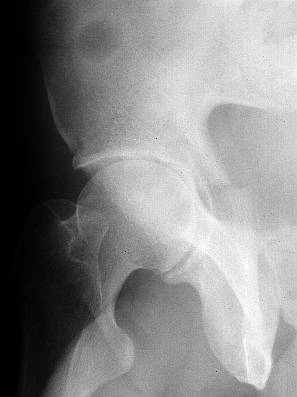

The iliac oblique reveals a displaced fracture of the posterior column, and it appears that the femoral head is not congruous with the acetabulum.

AP, obturator oblique films and a CT scan will better reveal the extent of the injury.

> The iliac oblique reveals a displaced fracture of the posterior column,

IMHO, it' s a transverse fr.